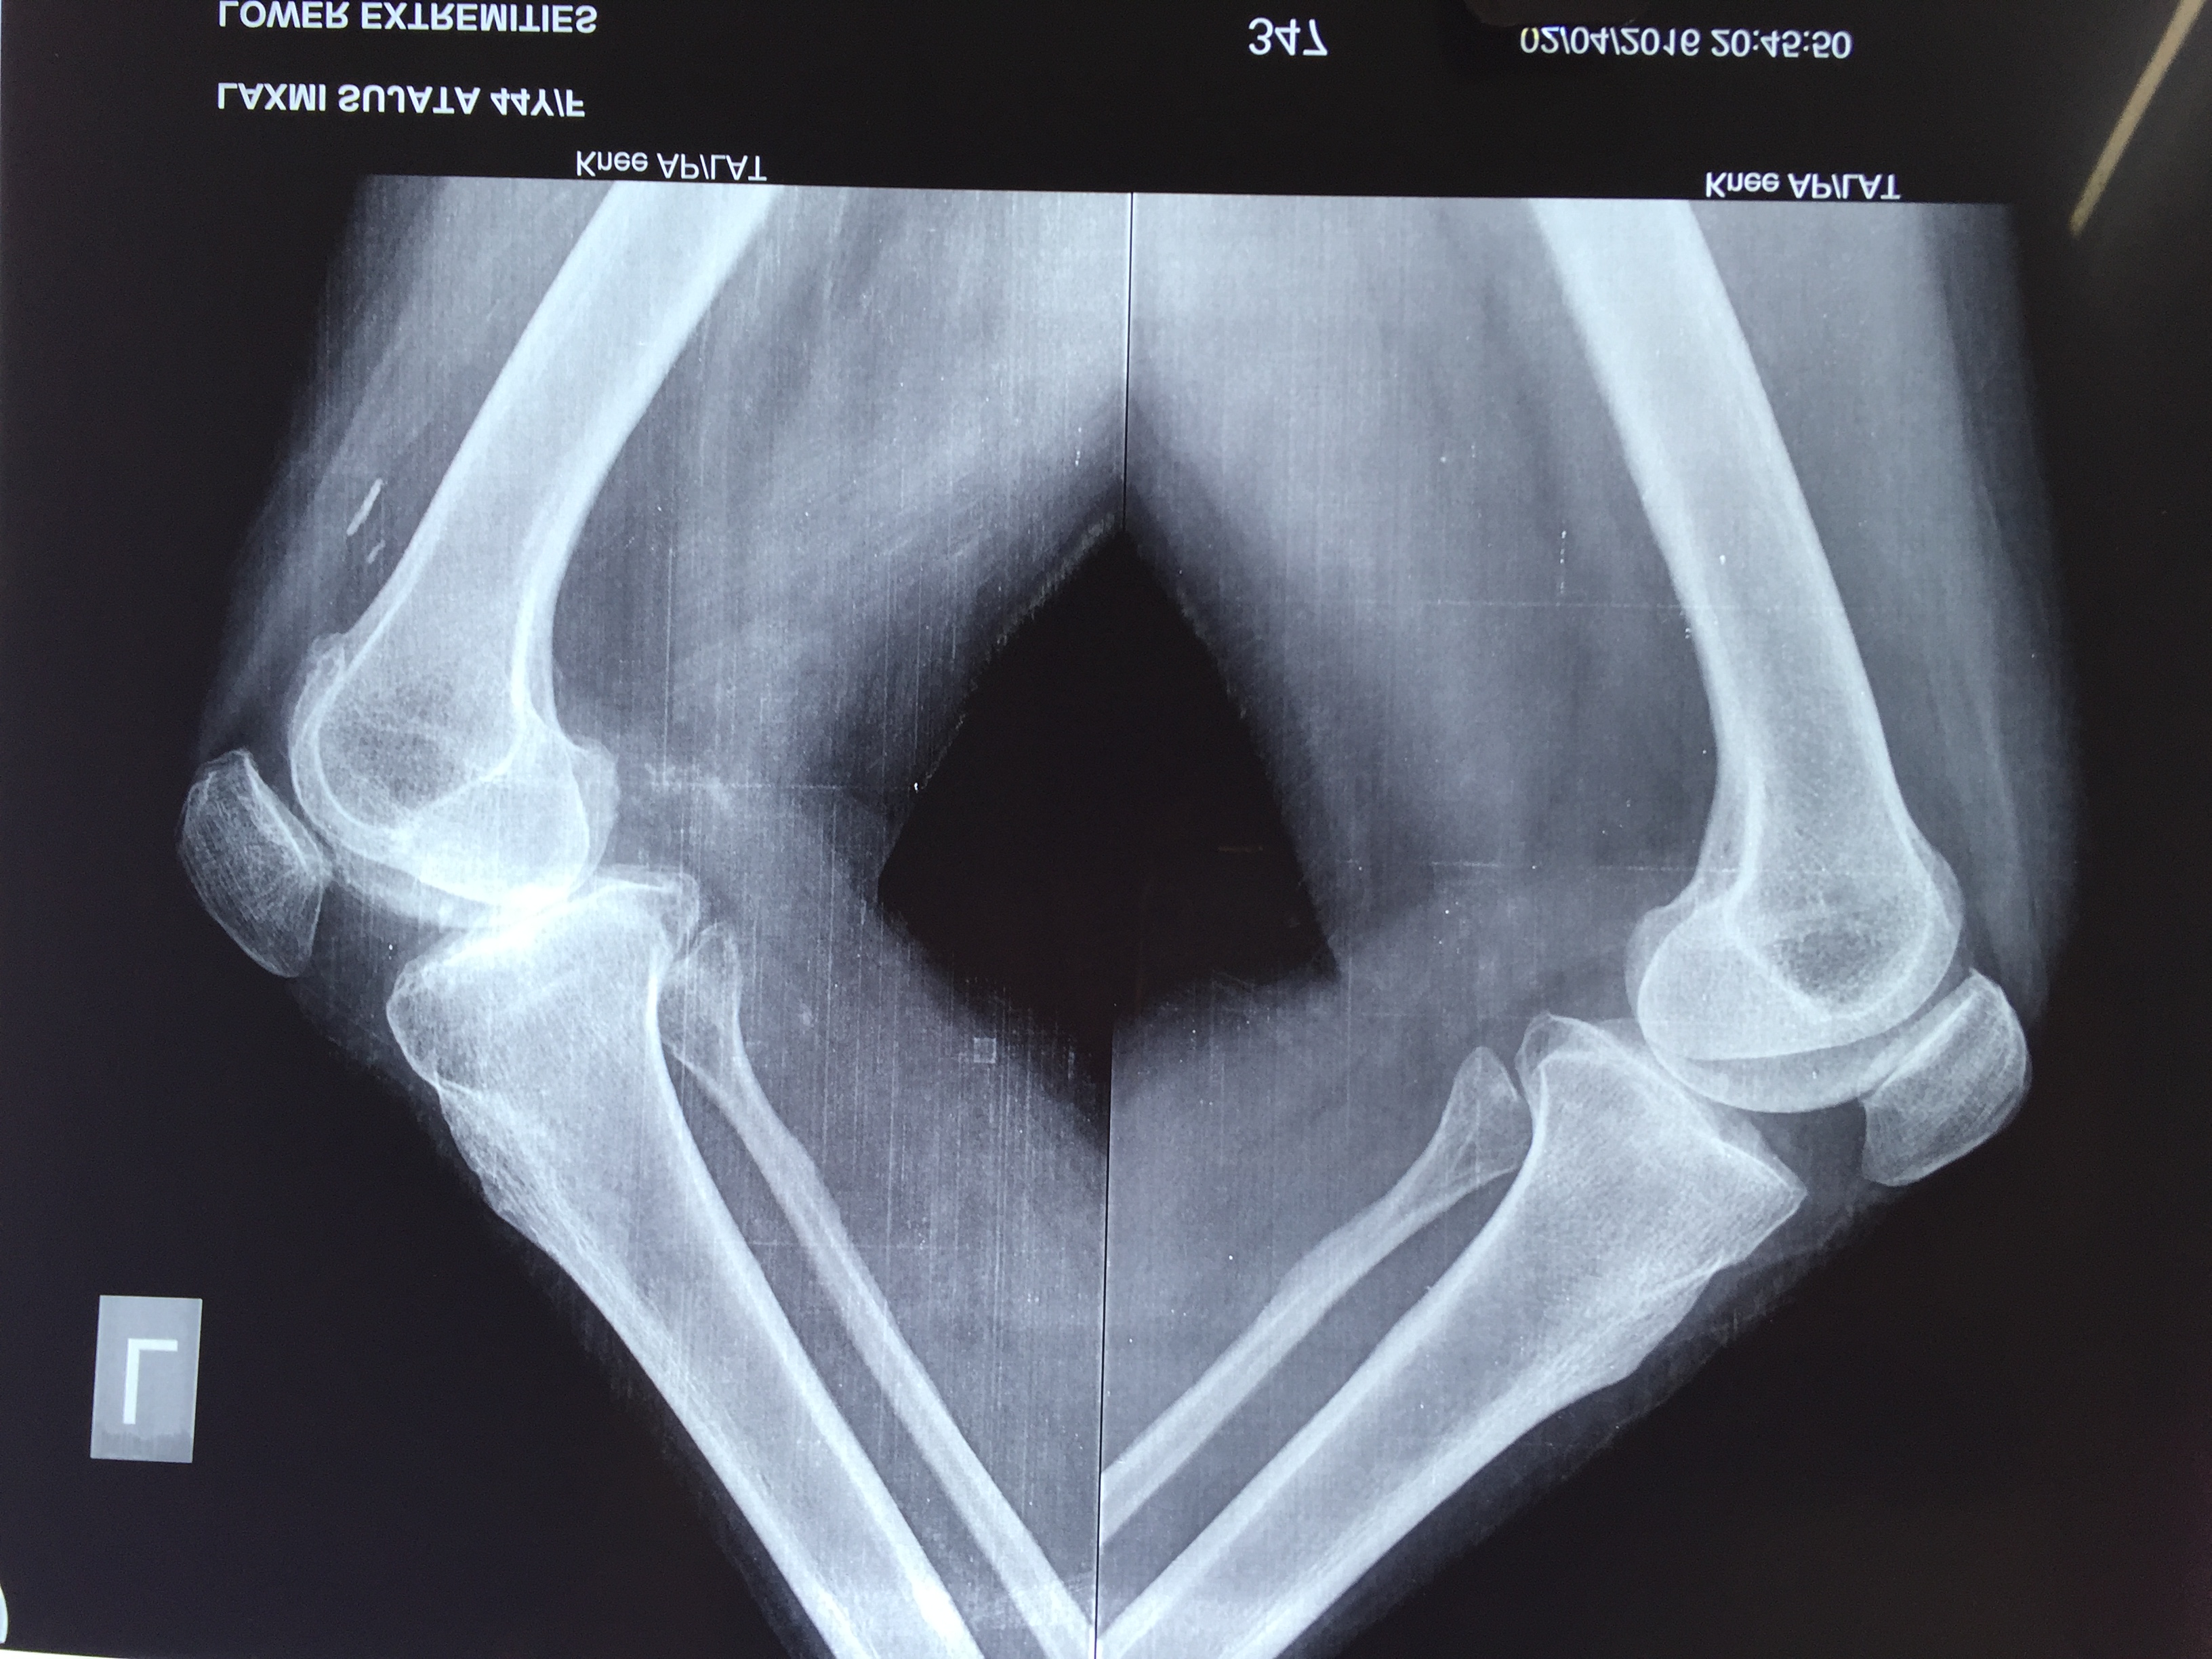

What is multi-ligament knee Injury?

Multiple ligament knee injuries happen when more than one of the knee’s ligaments is torn. They are less common than single ligament injuries.

What causes Multi-Ligament Knee Injury?

Multiple ligament knee injuries can occur during sports activities or through high-energy trauma, such as a fall from height or a car accident.

How Multi-ligament knee Injury diagnosed?

The most important way to initially diagnose these injuries is to review a thorough history with the patient to recall that their knee felt that it dislocated and slipped back in. It’s important to determine if this was solely their kneecap joint where there was a patellar (kneecap) dislocation or if it was the complete knee joint itself slipping out of place.

These injuries are very severe and potentially limb and life threatening. Thus, assessing for this and insuring that the patient’s knee function is intact, including both the status of the pulses to ensure that the artery is not injured as well as their sensation to ensure that there are no nerve injuries present is important.

How multi–Ligament Knee Injury Treated?

Nearly all cases of multiple ligament knee injury require surgery. The goal of surgery is to:

Restore knee stability

Regain full range of motion

Allow a return to athletic activities in the future

Before surgery, patients are prescribed physical therapy to work on regaining full motion and to decrease knee swelling. All patients wear a brace to protect the knee before surgery.